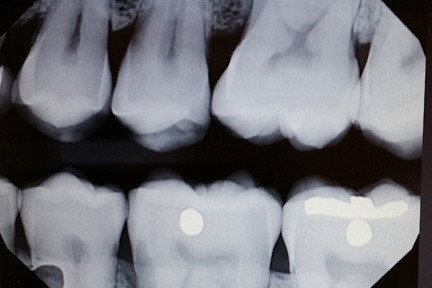

Five years later—and five years since my last tooth exam—I again found myself strapped to Dr. Berta’s skillful chair.

Like a vintage vehicle, the older I get, the more maintenance seems necessary to preserve my banged-up chassis. An x-ray and a few minutes under The Scraper proved that my teeth were no exception to this declining motor standard as my mouth bore early signs of gum disease. If my jaw wasn’t already pried open, it would’ve surely dropped as Berta informed me of this. She then said that four-hours of chiseling would be required to safeguard my not-so-pearly whites.

It’s strange to have hands and metal digging under your gums. It’s also strange to realize mid-treatment that your beard has gotten so out of control that the dentist needs to push your lip whiskers aside to properly do their art. Even more strange is leaving the clinic to kill time before catching a plane back home and finding that the only place within walking distance with Wi-Fi is a McCafé. Strangest of all is answering a phone call from an identified number (with post-dental numb gums) and hearing the voice of a relative you haven’t spoken to in years calling you from prison on a smuggled cell phone. Yes, this all happened.

I want to thank Berta for tending to my devil-may-care mouth. If you’re in Southern Ontario and in need of dental nurturing, be sure to visit Dr. Berta Bacic & Associates. I also want to thank Dean and the students of Armstrong Acting Studios for making me feel welcomed, and for letting me ramble about things I love. To all my friends in Toronto, ’til the next time.